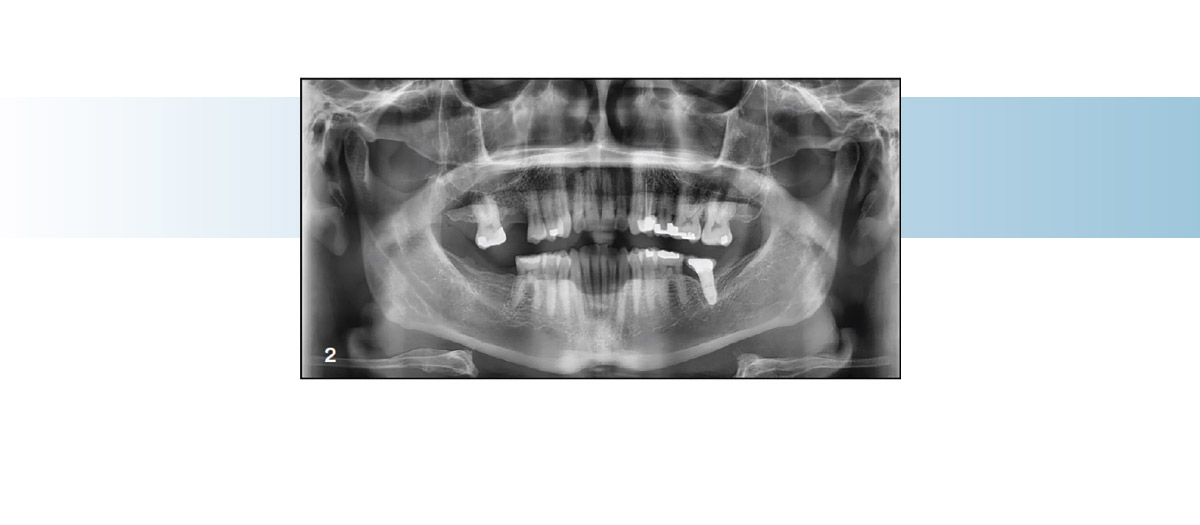

Fig. 2: Initial radiographic imaging.

We had a 45-year-old male patient approach us with the desire to improve his alignment, close a few small spaces (between UR2 and UR3) and prepare for dental implants in the UR6 and LR7 areas (Fig. 1). The patient’s chief complaints were crowding and minor spacing. He also had a Class I malocclusion with moderate lower crowding and mild upper crowding (U&L, 3x3), along with a need for improved arch development and coordination (Figs. 2 and 3).

When he first walked into the practice, the patient was scheduled to receive two implants in three months, and he had existing crowns placed on the LL7 and UL4. Seeking a comprehensive treatment plan for his implants and alignment, the patient expressed interest in an aesthetic corrective solution. Given the choice of brackets or clear aligners, he decided on aligners, purely for their aesthetic qualities.